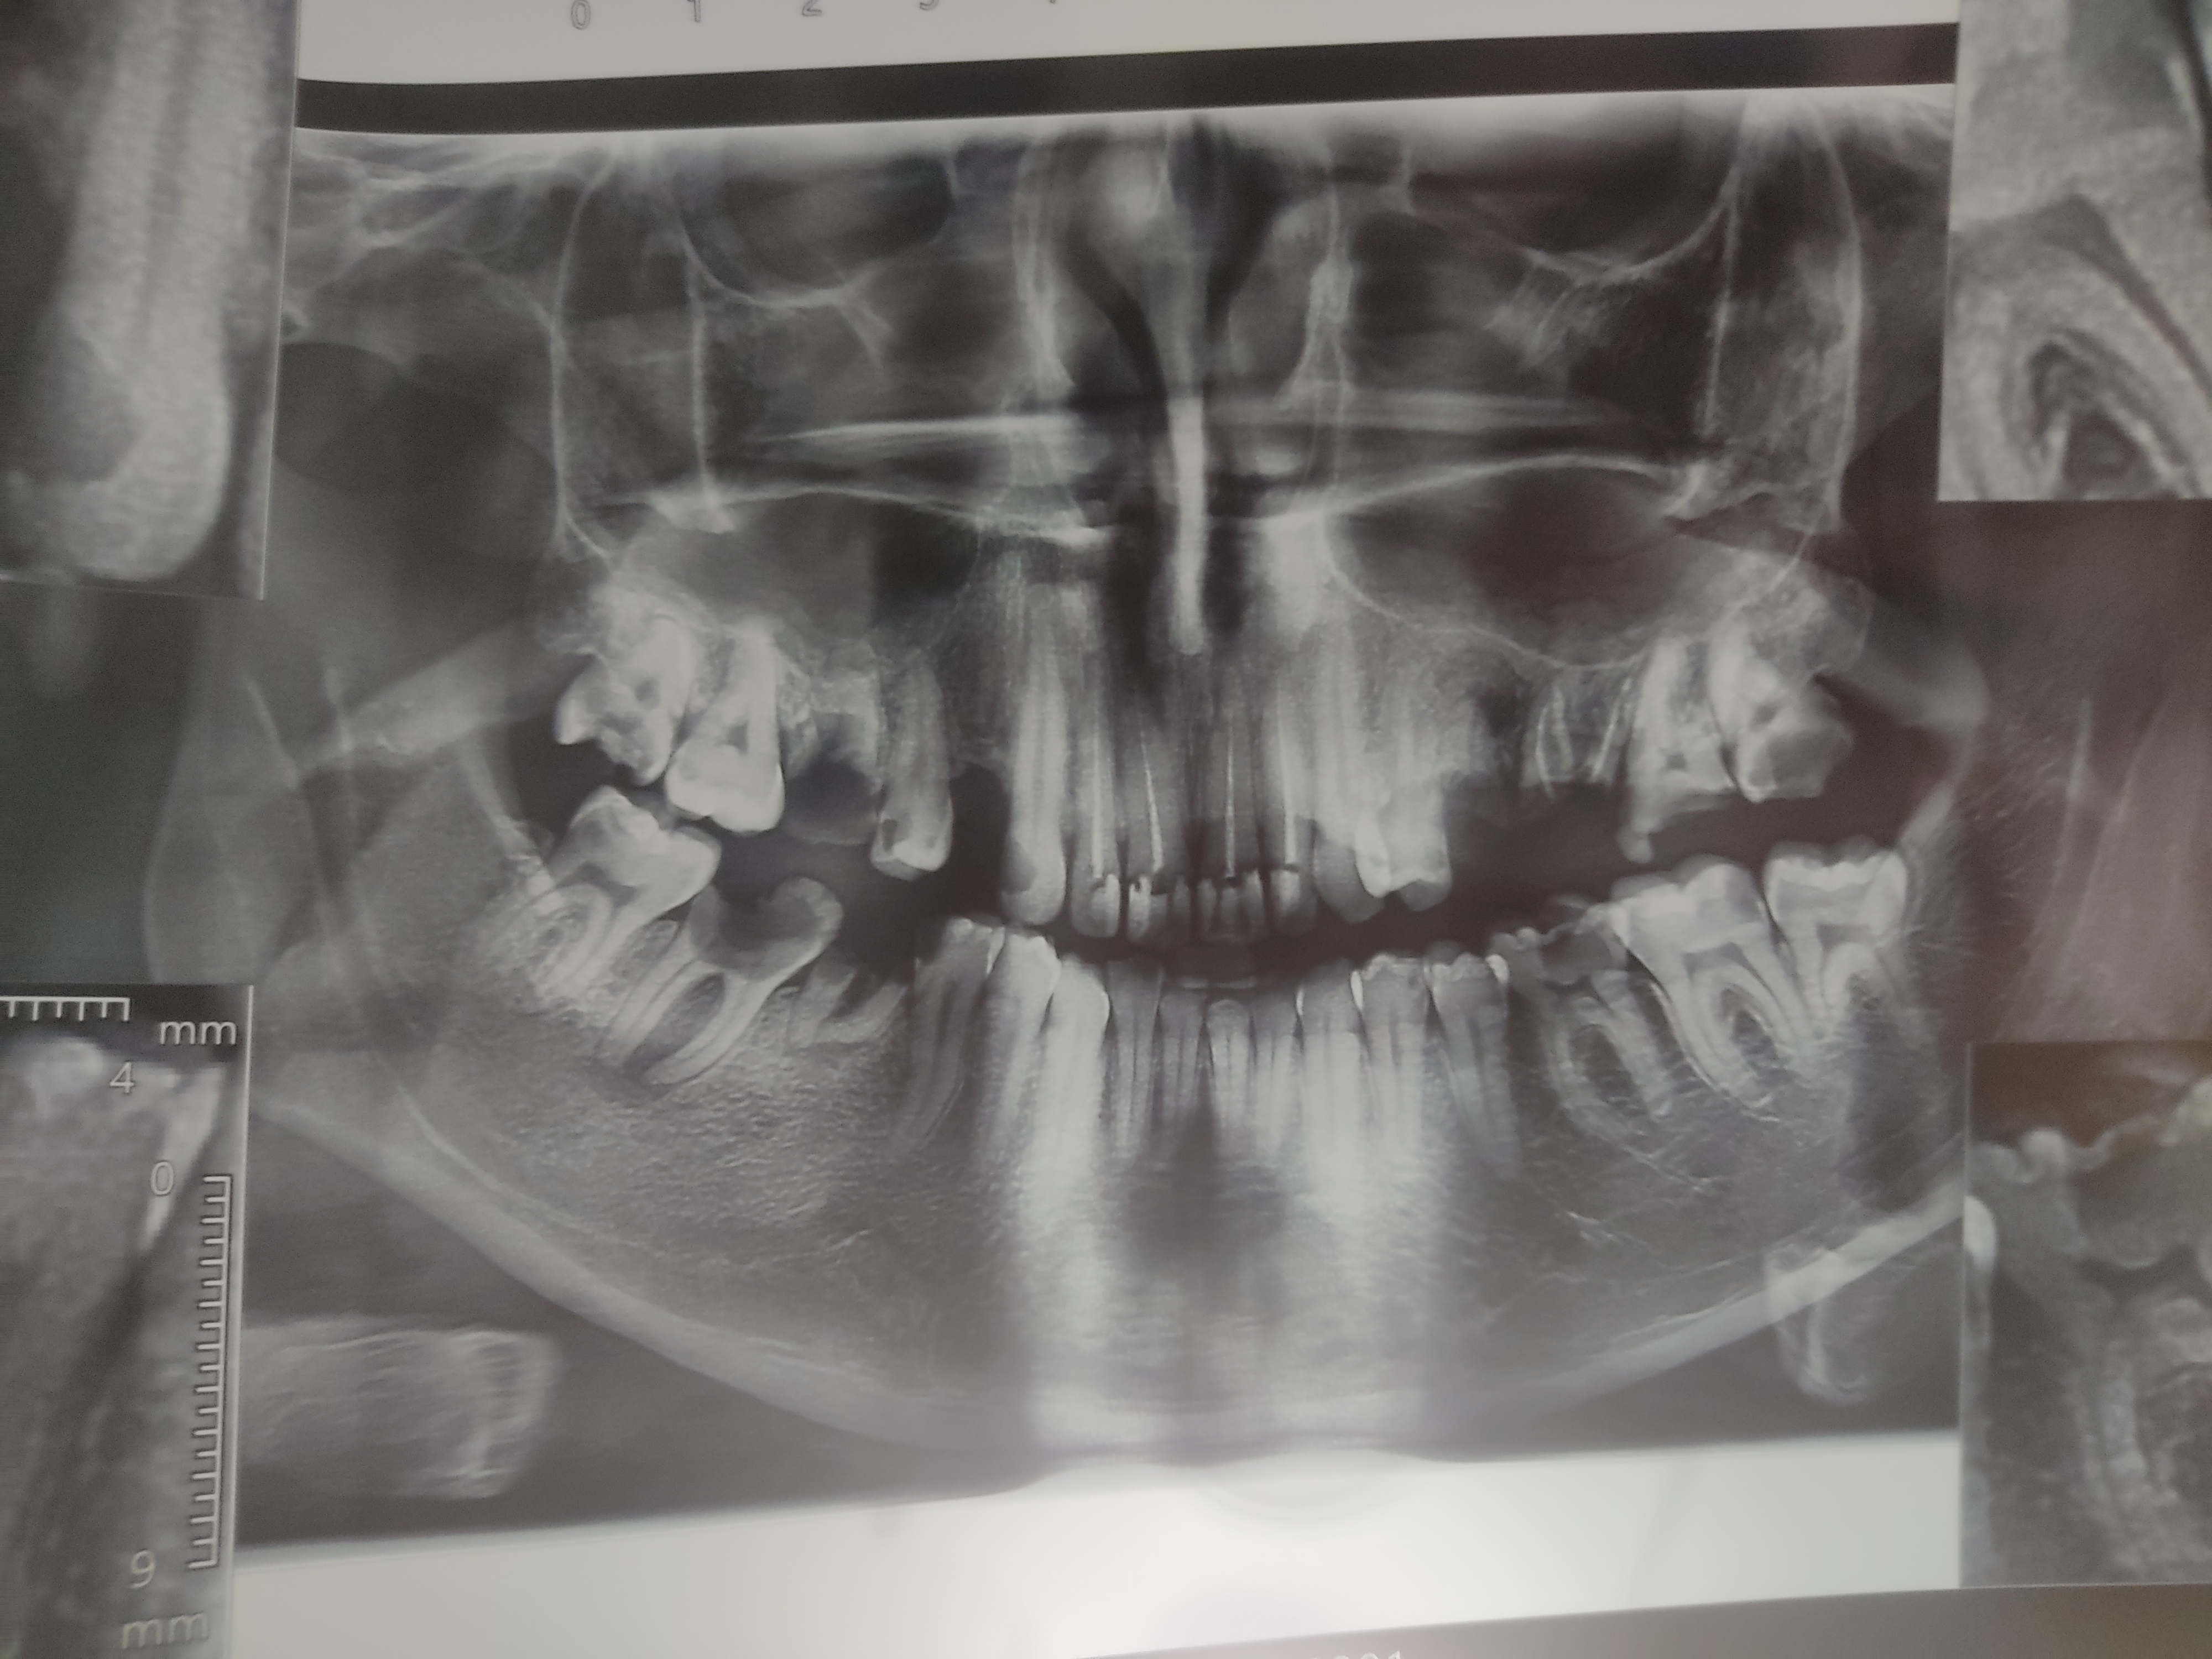

آنچه از عکس بهطور احتمالی دیده میشه:

1️⃣ دندانهای عقل (۴ تا)

• پایینِ چپ و پایینِ راست: نهفته و کج هستن (تقریباً افقی) و به دندان جلویی فشار میارن

👉 معمولاً نیاز به کشیدن دارن چون:

• تمیز نمیشن

• باعث پوسیدگی دندان کناری میشن

• در آینده درد و عفونت میدن

• بالاها: بهنظر یا نیمهنهفتهان یا ریشههاشون نامناسبه

👉 اغلب کشیدن پیشنهاد میشه (مخصوصاً اگر درد یا پوسیدگی دارن)

📌 جمعبندی عقلها:

احتمالاً ۳ تا یا ۴ تا دندان عقل باید کشیده بشن

2️⃣ دندانهای آسیاب کناری عقل (۷ها)

• بعضی از آسیابهای عقب در تماس با دندان عقل آسیب دیدن

• اگر پوسیدگی تا ریشه نرفته باشه:

👉 میشه عصبکشی روکش و نگهشون داشت

• اگر:

• ریشهها تحلیل شدید دارن

• یا عفونت انتهای ریشه واضحه

👉 اون دندان هم ممکنه غیرقابل نگهداشت باشه

باز هم تأکید میکنم: برآورد از روی عکس پانورامیکه، نه تشخیص قطعی.

📊 جمعبندی احتمالی از روی این عکس

🔴 کشیدنیها (گفتم قبلاً، برای مقایسه):

• دندانهای عقل: ۳ تا یا ۴ تا

🦷 دندانهایی که احتمالاً

نیاز به عصبکشی روکش

دارن

۲ تا (احتمالاً ۳ تا)

معمولاً اینها هستن:

• آسیابهای کنار دندان عقل پایین

• یکی در سمت راست، یکی در سمت چپ

(بهخاطر فشار، پوسیدگی عمقی یا درگیری نزدیک عصب)

👉 اگر عفونت انتهای ریشه خیلی شدید نباشه:

• عصبکشی روکش = قابل نگهداشتن

🟡 دندانهایی که فقط

ترمیم (پرکردن)

میخوان

✅ حدود

۲ تا ۳ تا

• پوسیدگی سطحی یا متوسط

• هنوز به عصب نرسیده

• با پرکردن معمولی یا کامپوزیت حل میشه

🔍 جمعبندی عددی نهایی (تقریبی)

• 🦷 عصبکشی روکش: ۲ (حداکثر ۳)

• 🦷 ترمیم ساده: ۲ تا ۳

• 🦷 کشیدن: ۳ تا ۴ (عقلها)